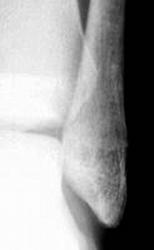

жалобы на незначительные боли в области левой пятки. несколко меяцев назад была травма,после которой полявиась припухлость в области пятки.К врачу не обращался. После мед осмотра в школе направлен на рентгенографию.

Навскидку - костная киста.

киста пяточной кости и вальгусная деформация голеностопного сустава

1- псевдокиста пяточной кости, данная локализация характерная, но клинику она обычно не даёт а если и дает то редко, я уже выкладывал случай:

2-остеомиелит, возможно посттравматический;

3- менее вероятно доброкачестванная новообразование;

Мы довольно часто встречаемся с такой патологией - костная киста, при проведении экспертизы годности к военной службе, при рентгенометрии "продольного плоскостопия", и довольно часто это патологическое состояние бывает с одной стороны.